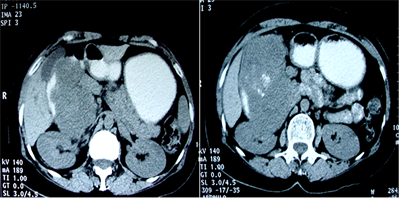

CT scan, performed with oral and intravenous contrast, upheld the findings of ultrasound revealing a large heterogeneous tissular mass in the pancreatic head, with central necrosis and calcifications (Figure 2). It showed an intense heterogeneous enhancement in the arterial phase. This mass was bounded in front by the gall bladder which is repressed, in the back by the right kidney with apparent para renal fat invasion and laterally, by digestive structures (small bowl and colon). The corporeal and caudal portions of the pancreas were normal. Moreover, intrahepatic and extrahepatic bile ducts were not dilated and no metastatic localisation was detected.

Figure 2. Abdominal computed tomography scan. (a) Computed tomography scan with oral contrast showing the calcifications within the pancreatic head mass which is repressing the gall bladder; (b) Computed tomography scan performed after oral and venous contrast in the portal phase showing an intense heterogeneous enhancement associated with necrosis within the mass; (c) Computed tomography scan performed after oral and venous contrast in the tardive phase.